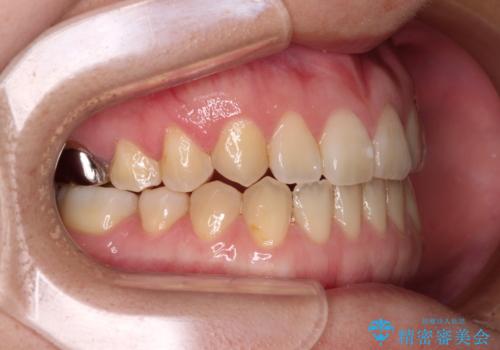

受け口で開咬を急速拡大装置とインビザラインで改善 欠損部分はインプラントにて補綴治療

- 前歯の開咬と、受け口による咬み合わせの悪さを気にして来院された患者様です。

左上は後続永久歯の欠損によりスペースがあり、矯正治療と並行してインプラントあるいはブリッジによる補綴治療が必要な状況でした。

上顎歯列が狭窄していたため、急速拡大装置により上顎骨を側方に拡大し、その後インビザラインにて矯正治療を行うこととしました。

矯正治療と並行してインプラントによる補綴治療を行うこととしました。